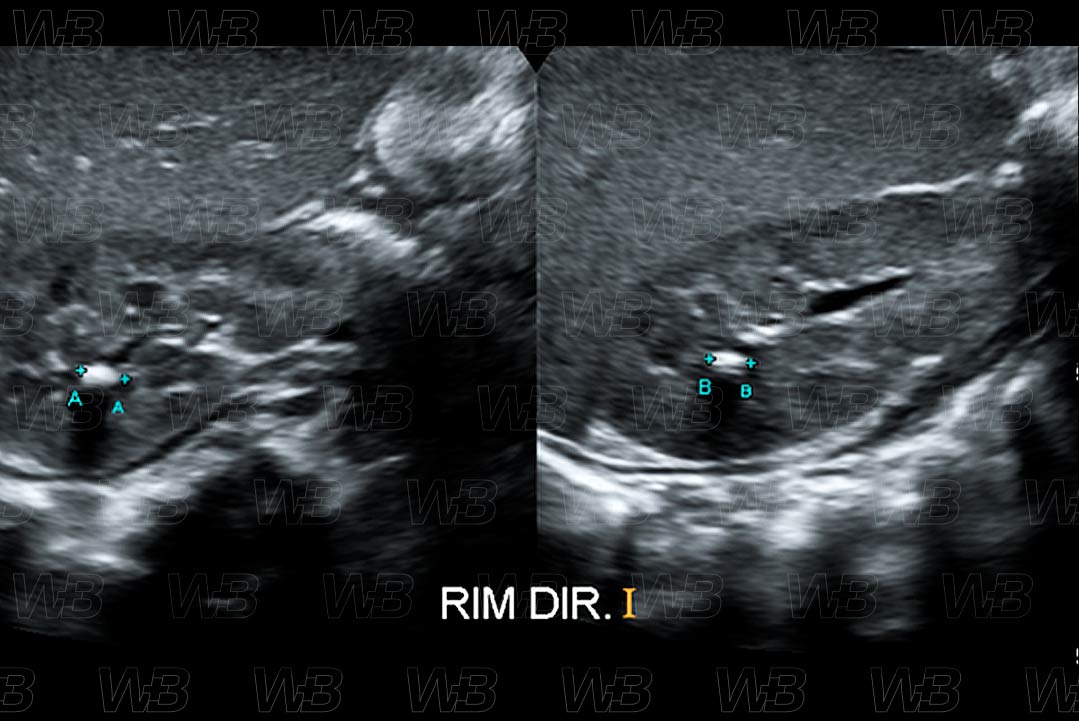

Texto alternativo para a imagem Figura 3. Créditos: Dra. Elazir Mota - Rio de Janeiro/RJ

Descrição da figura 3: Ultrassonografia do aparelho urinário. Presença de imagem hiperecogênica, com sombra acústica posterior, no terço superior do rim direito, compatível com cálculo renal.

• Ultrassonografia do abdome: Po de ser um método utilizado principalmente na população pediátrica, pela não presença de radiação ionizante. É um bom método para cálculos com mais de 3-4 cm. Aparece na imagem como foco hiperecogênico, com sombra acústica posterior e com artefato de twinkle no Doppler colorido, podendo estar associado ou não ao artefato em cauda de cometa;